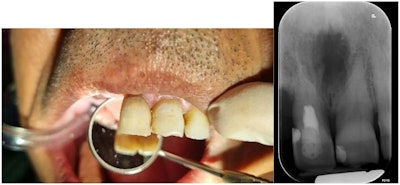

To treat the patient, he underwent root canal therapy limited to the necrotic coronal pulp up to the dentin bridge. Internal bleaching followed to improve the discoloration, and then a restoration with composite resin was completed.

At his three-month follow-up, a radiograph showed no problems, according to the case report.

Figure 4: Photo and periapical radiography after root canal therapy and tooth restoration.